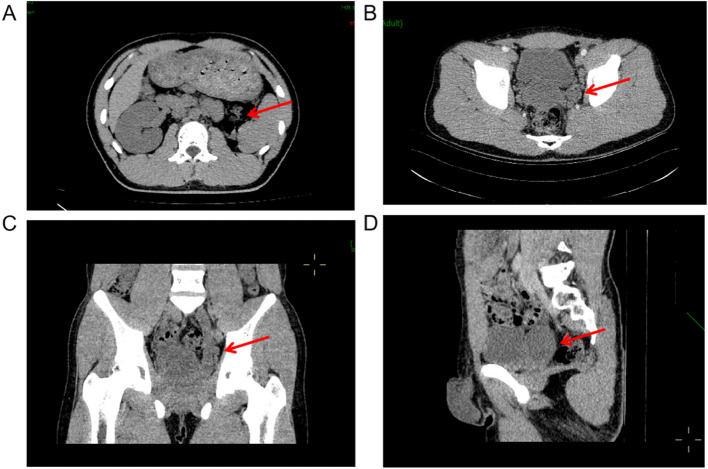

Case presentation: We report the case of an 18-year-old male presenting with urinary pain and was diagnosed with right renal agenesis and a left seminal vesicle cyst following comprehensive imaging. The patient also experienced perineal pain and urgency, without symptoms of frequent urination, dysuria, or hematuria, and no familial history of genitourinary anomalies was documented. He successfully underwent laparoscopic resection of a pelvic mass, with pathological examination confirming a seminal vesicle cyst. Postoperative recovery was uneventful. Whole exome sequencing of blood and tissue samples highlighted myeloma overexpressed gene (MYEOV), B melanoma antigen family member (BAGE), and N-acetylated-alpha-linked acidic dipeptidase 2 (NAALAD2) as potential mutated genes related to Zinner syndrome. Additionally, two predisposing genetic variants were identified.